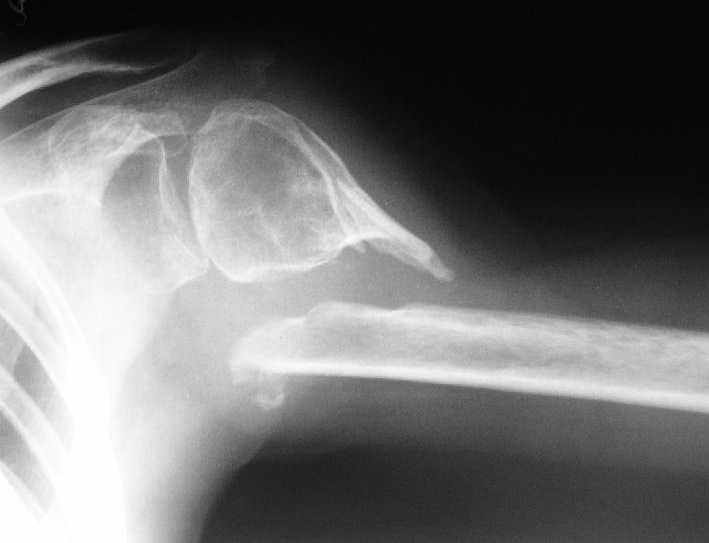

[Ortho] Несращение плеча, деформация головки

Больная 40 лет, множественная травма в июне 2007 года. Лечилась в городской больнице.

Повреждение проксимального отдела плеча вели  консервативно в гипсовой

повязке. В настоящее время больную беспокоят боли в области плечевого

сустава, слабость верхней конечности. Амплитуда движений в плечевом

суставе в пределах 30-40 градусов. Пациентка хотела бы увеличить объем

движений и силу.

Движения сейчас в основном за счет ложного сустава. Варианты -

остеосинтез, артролиз, эндопротезирование, оставить как есть. Как-то

ни один однозначно не привлекает.